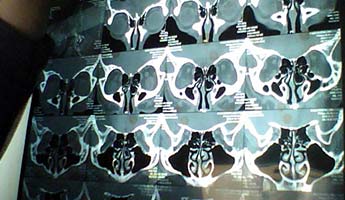

鼻炎

【技术】微创鼻炎治疗术

治疗鼻炎哪种方法效果好?

【已解决】鼻炎的较好治疗方法